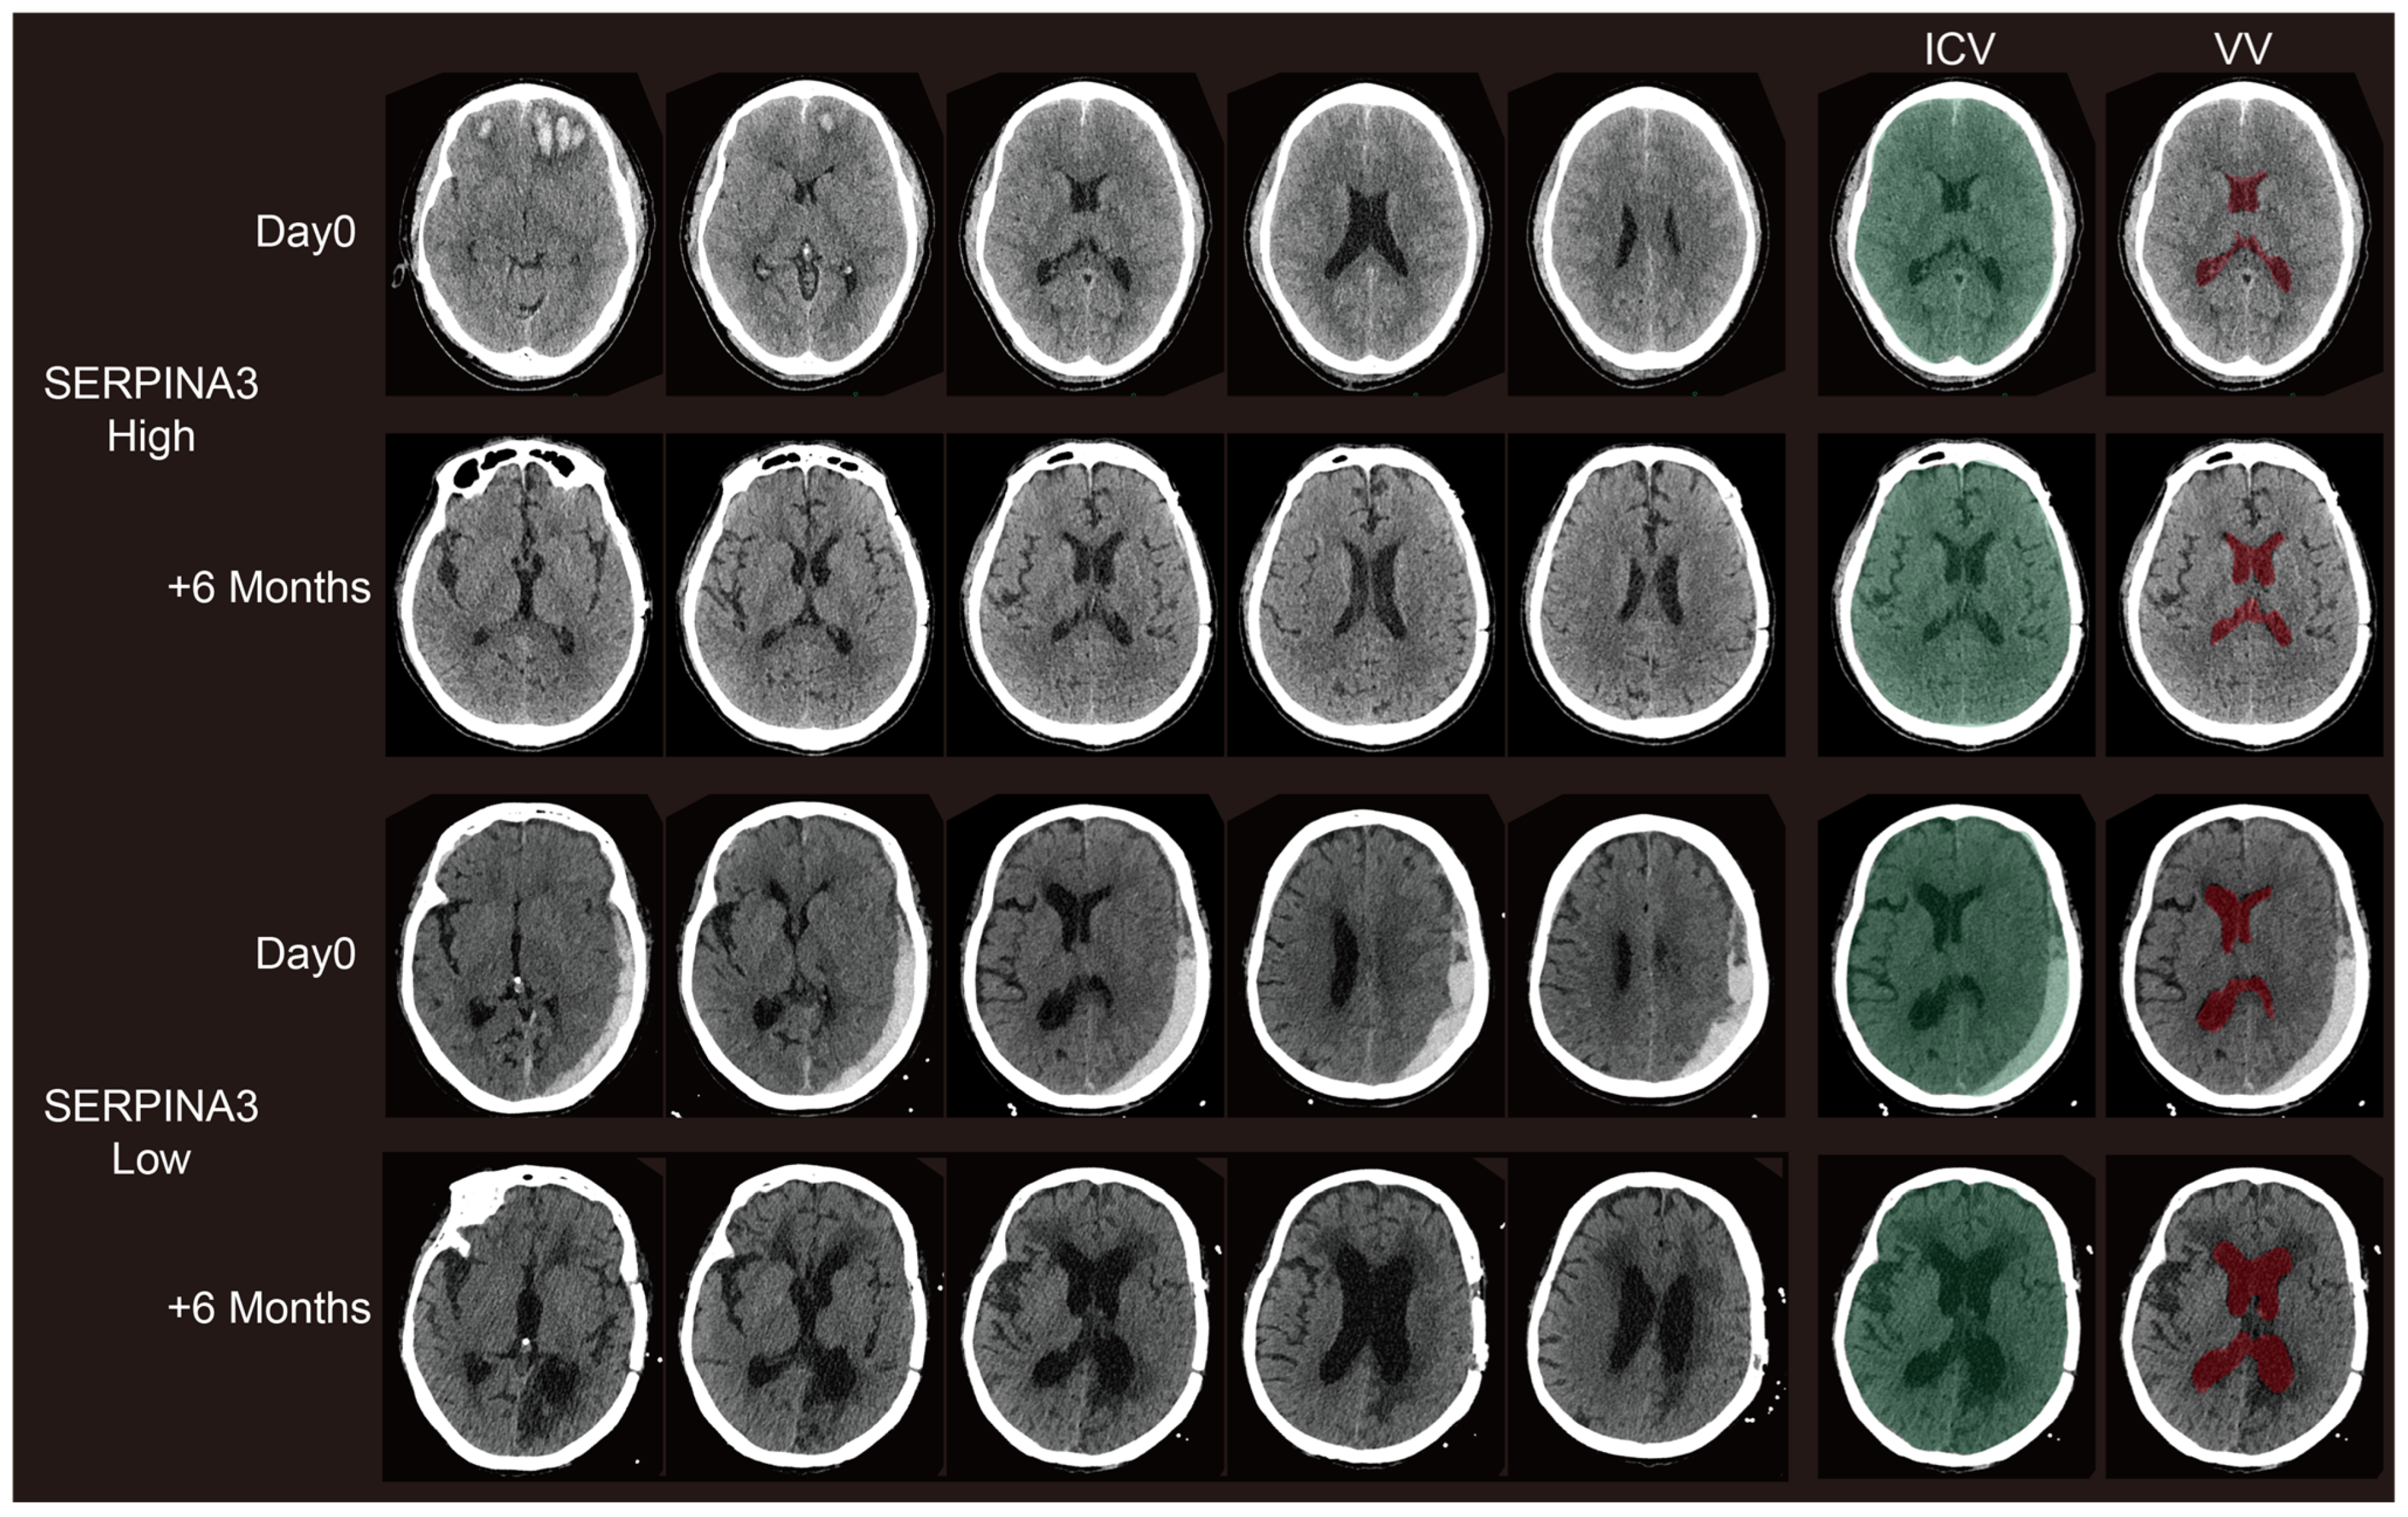

3.4. Long-Term Structural Changes on CT Images Correlate with Preoperative Serum SERPINA3 Levels